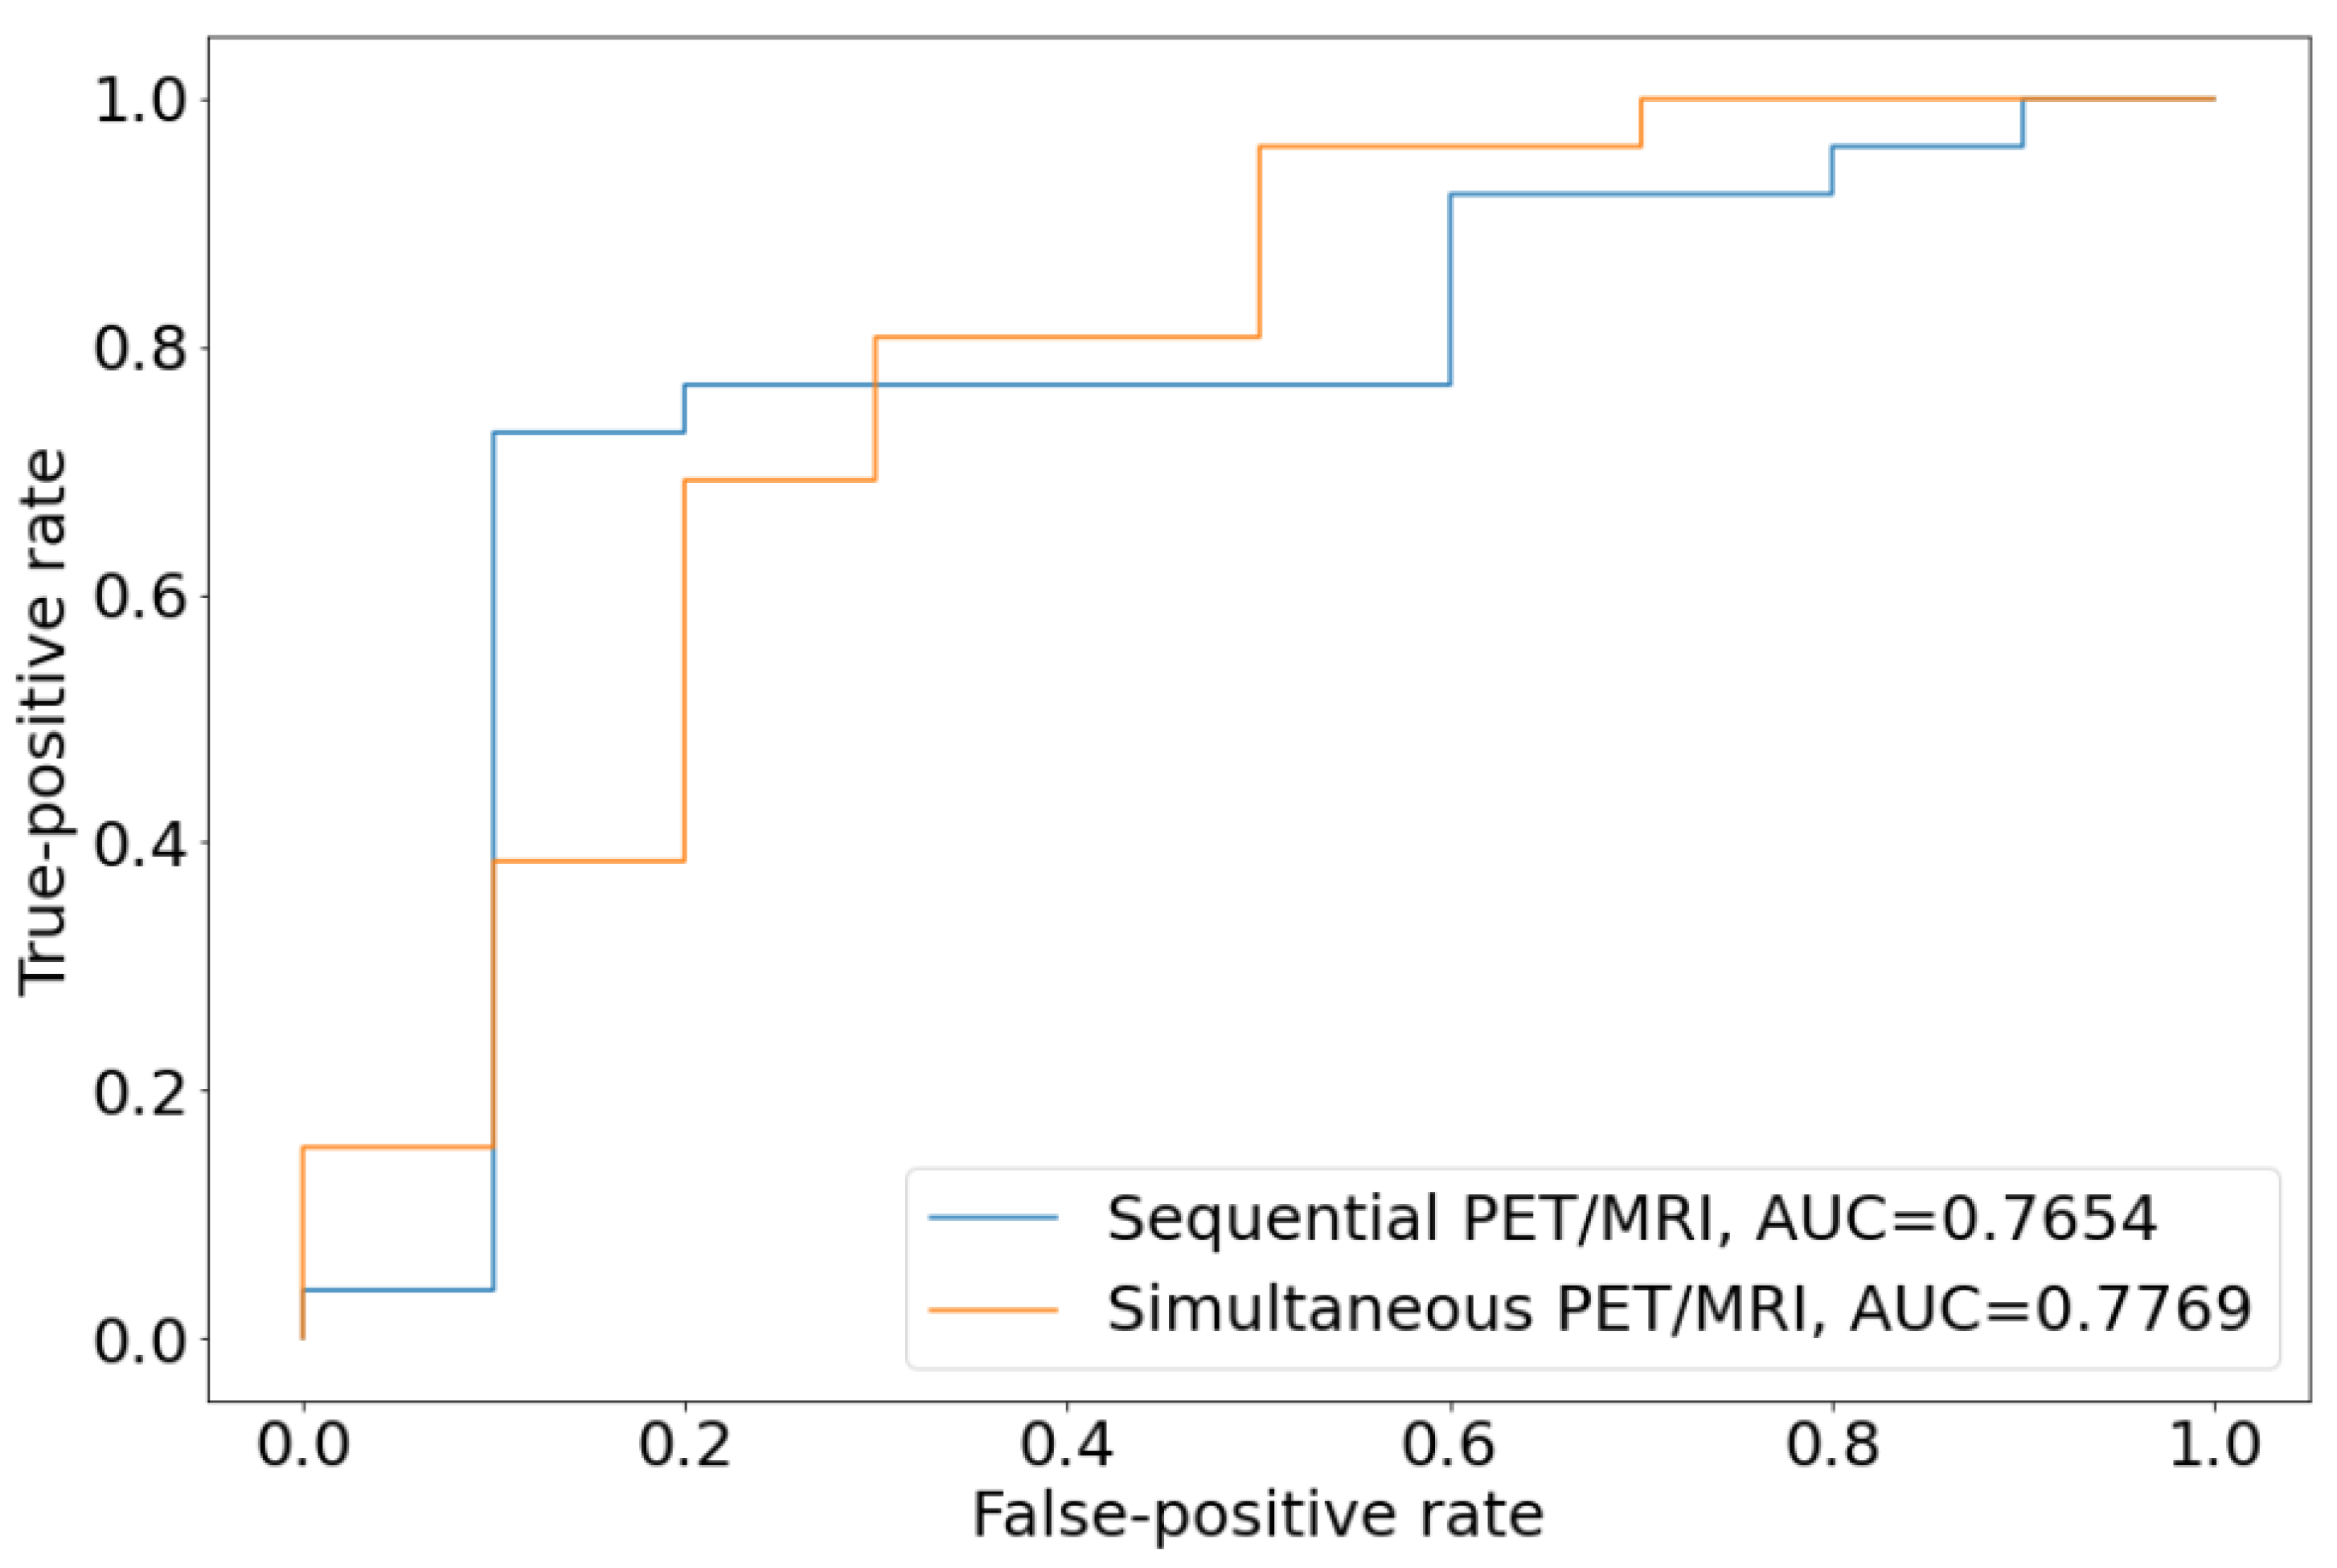

3.3. Diagnostic Power of Sequential PET/MRI Acquisition